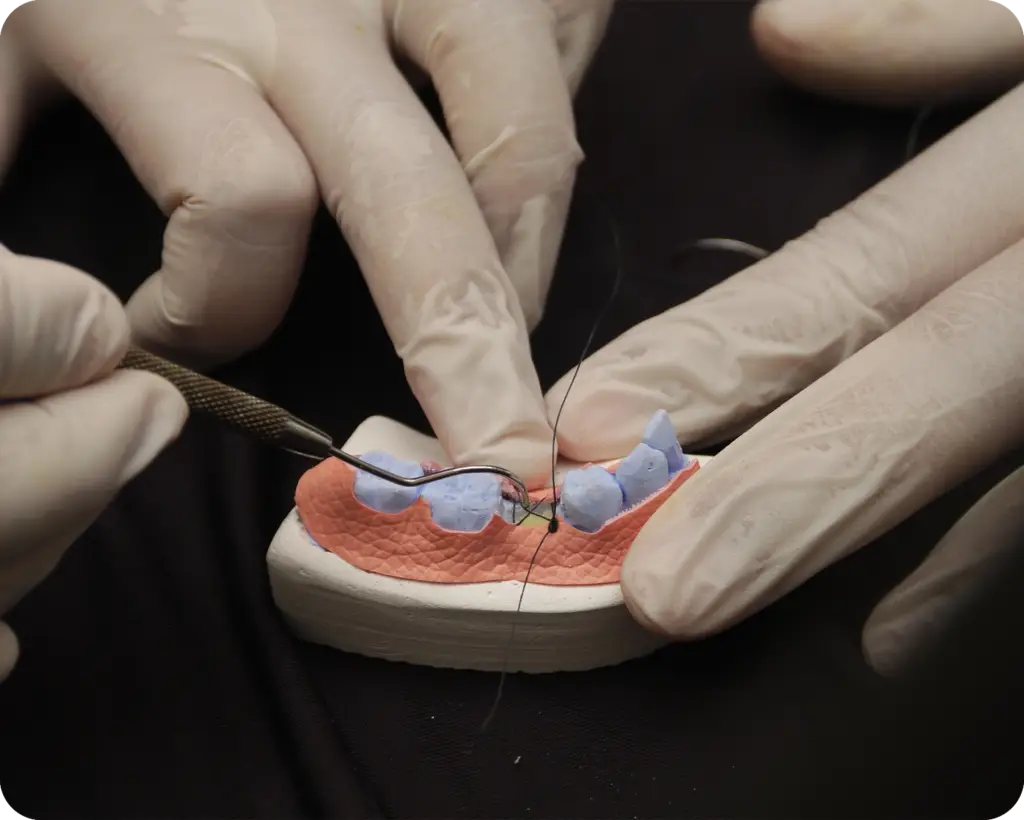

Cirugía de tejido blando: En situaciones en las que se requiere un mejor contorno de los tejidos blandos alrededor de los implantes dentales, se puede realizar cirugía de tejido blando. Esto puede incluir procedimientos como el aumento de encía, la remodelación de la forma de la encía o la corrección de problemas estéticos y funcionales relacionados con la apariencia de las encías alrededor de los implantes dentales.